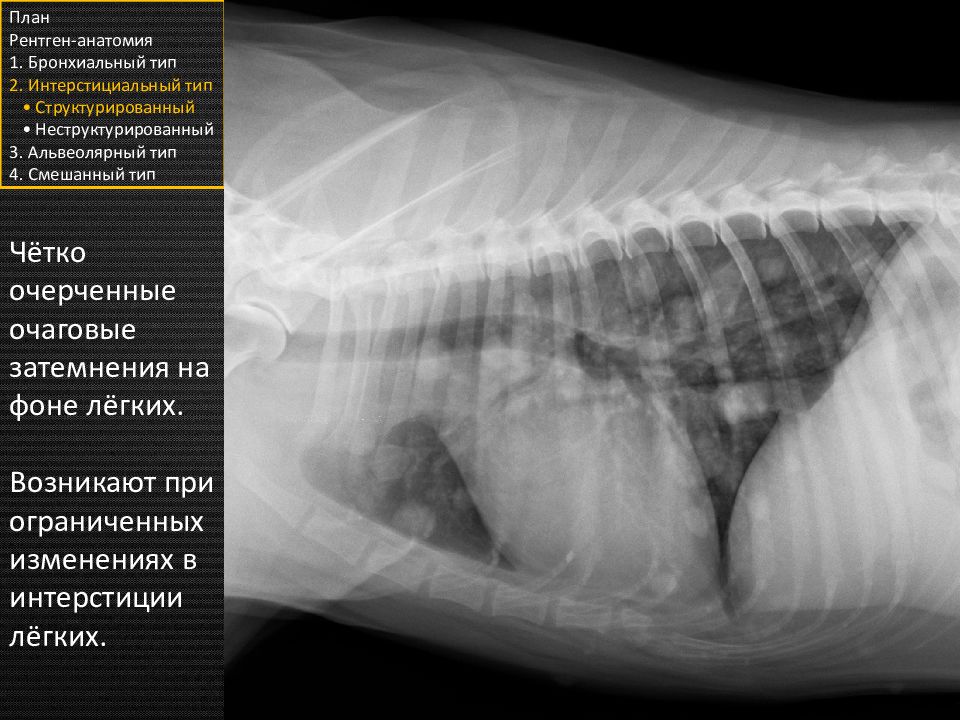

Чётко очерченные очаговые затемнения на фоне лёгких. Возникают при ограниченных изменениях в интерстиции лёгких. План Рентген-анатомия 1. Бронхиальный тип 2. Интерстициальный тип • Структурированный • Неструктурированный 3. Альвеолярный тип 4. Смешанный тип